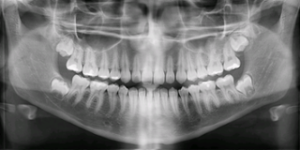

Panoramic X-ray – Why you need one

Why is a current panoramic x-ray important? When coming to our office for a dental procedure, it is very important for us to have a current x-ray. Current x-rays (also known as radiographs) are essential for accurate diagnosis. It is important for our doctors to see all areas of the face and jaws that are […]